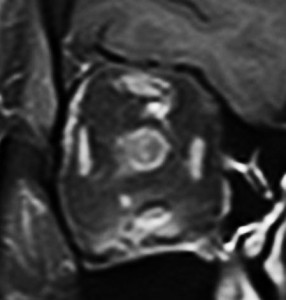

放射線治療をした例

鞍結節部から視神経管を伝わり視神経鞘に伸びていた例です。鞍結節部と視神経管での視神経圧迫があったのでそこを除圧するために摘出したのですが,グレード2の髄膜腫で再発しました。下のMRIは,放射線治療 50Gy/25frしてから5年後の画像です。腫瘍は大きくなっていませんし,右の視力はVd 0.5あり,有用視力といえるほどの視野ではありませんが,視野は上の方で残っています。